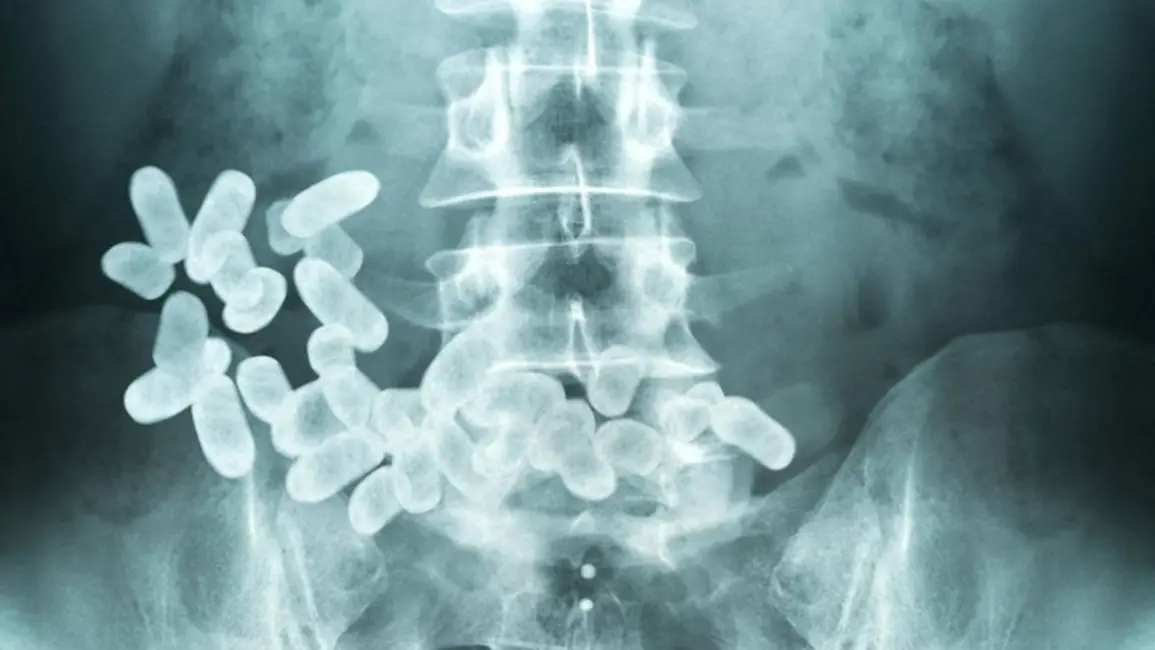

La famosas cápsulas de cocaína tienen un 56 por ciento de letalidad en su transporte vía intestinos. Archivo

Con la premura del caso, porque se trata de salvar una vida humana, el hombre fue trasladado hacia un centro asistencial para su examen radiológico y una vez confirmado que llevaba la carga ilegal, se le hizo un tratamiento para que expulsara las cápsulas de manera natural.

Luego se comprobó que el sujeto llevaba en total 113 cápsulas de cocaína de alta pureza, pero sorpresivamente el hombre aseguró que estaba algo apurado porque debía abordar un vuelo desde Ezeiza hacia Alemania y que el mismo tenía fecha para hoy sábado.